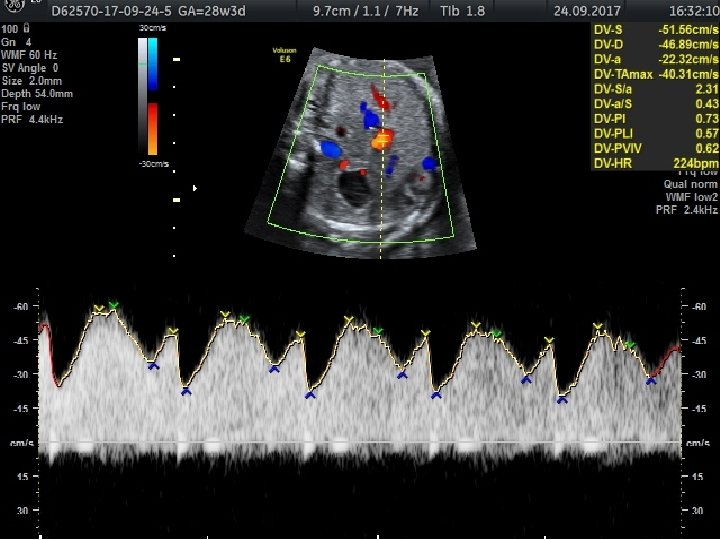

FETAL BÜYÜME BOZUKLUKLARINDA TAKİP VE DOĞUM • Günlük pratikte gelişme gerilikli fetusların takibi, ultrasonografi ile fetal biyometri ve amniyotik sıvı miktarının belirli aralıklarla ölçülmesi ile ve nonstres test veya biyofizik profil gibi antepartum fetal iyilik hali testleri ile yapılmaktadır. • Plasental yetmezliğe bağlı gelişen fetal gelişme geriliğinde standart fetal izlem ile birlikte fetal arterial/venöz dolaşımın Doppler değerlendirmesinin nonstres test ve biyofizik profili ile birlikte kullanımının daha iyi fetal sonuçlar ile ilişkili olduğu gösterilmiştir.

Obstetrik Doppler Ultrasonografi • Umblikal arter Doppler’i en yaygın olarak kullanılan fetal Doppler değerlendirmesidir ve en fazla kullanılan Doppler parametresidir. • Orta serberal arter Doppler • Umblikal arter Doppler değerlendirmesinde direnç artışı, diyastol sonu akımda kayıp veya ters dönme saptanması , artmış perinatal mortalite hızı ile ilişkili olmakla birlikte fetal gelişme geriliği olgularında doğum zamanlamasının belirlenmesini de etkilemektedir.

• Duktus venosus Doppler’inin kötü perinatal sonuçları tahmin etmedeki katkısı sınırlı olmakla birlikte yenidoğan sonuçlarını öngörmede en önemli kardiyovasküler parametre duktus venosus Doppler’idir.